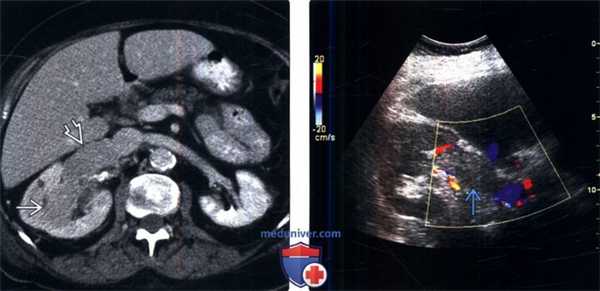

(Слева) КТ с контрастированием, аксиальная проекция: у женщины 60 лет выявлено контрастируемое образование в средней части правой почки с опухолевым тромбозом правой почечной вены. Обратите внимание на значительное расширение почечной вены.

(Справа) Цветовое допплеровское картирование: у этой же пациентки выявлен протяженный эхогенный тромб в правой почечной вене..